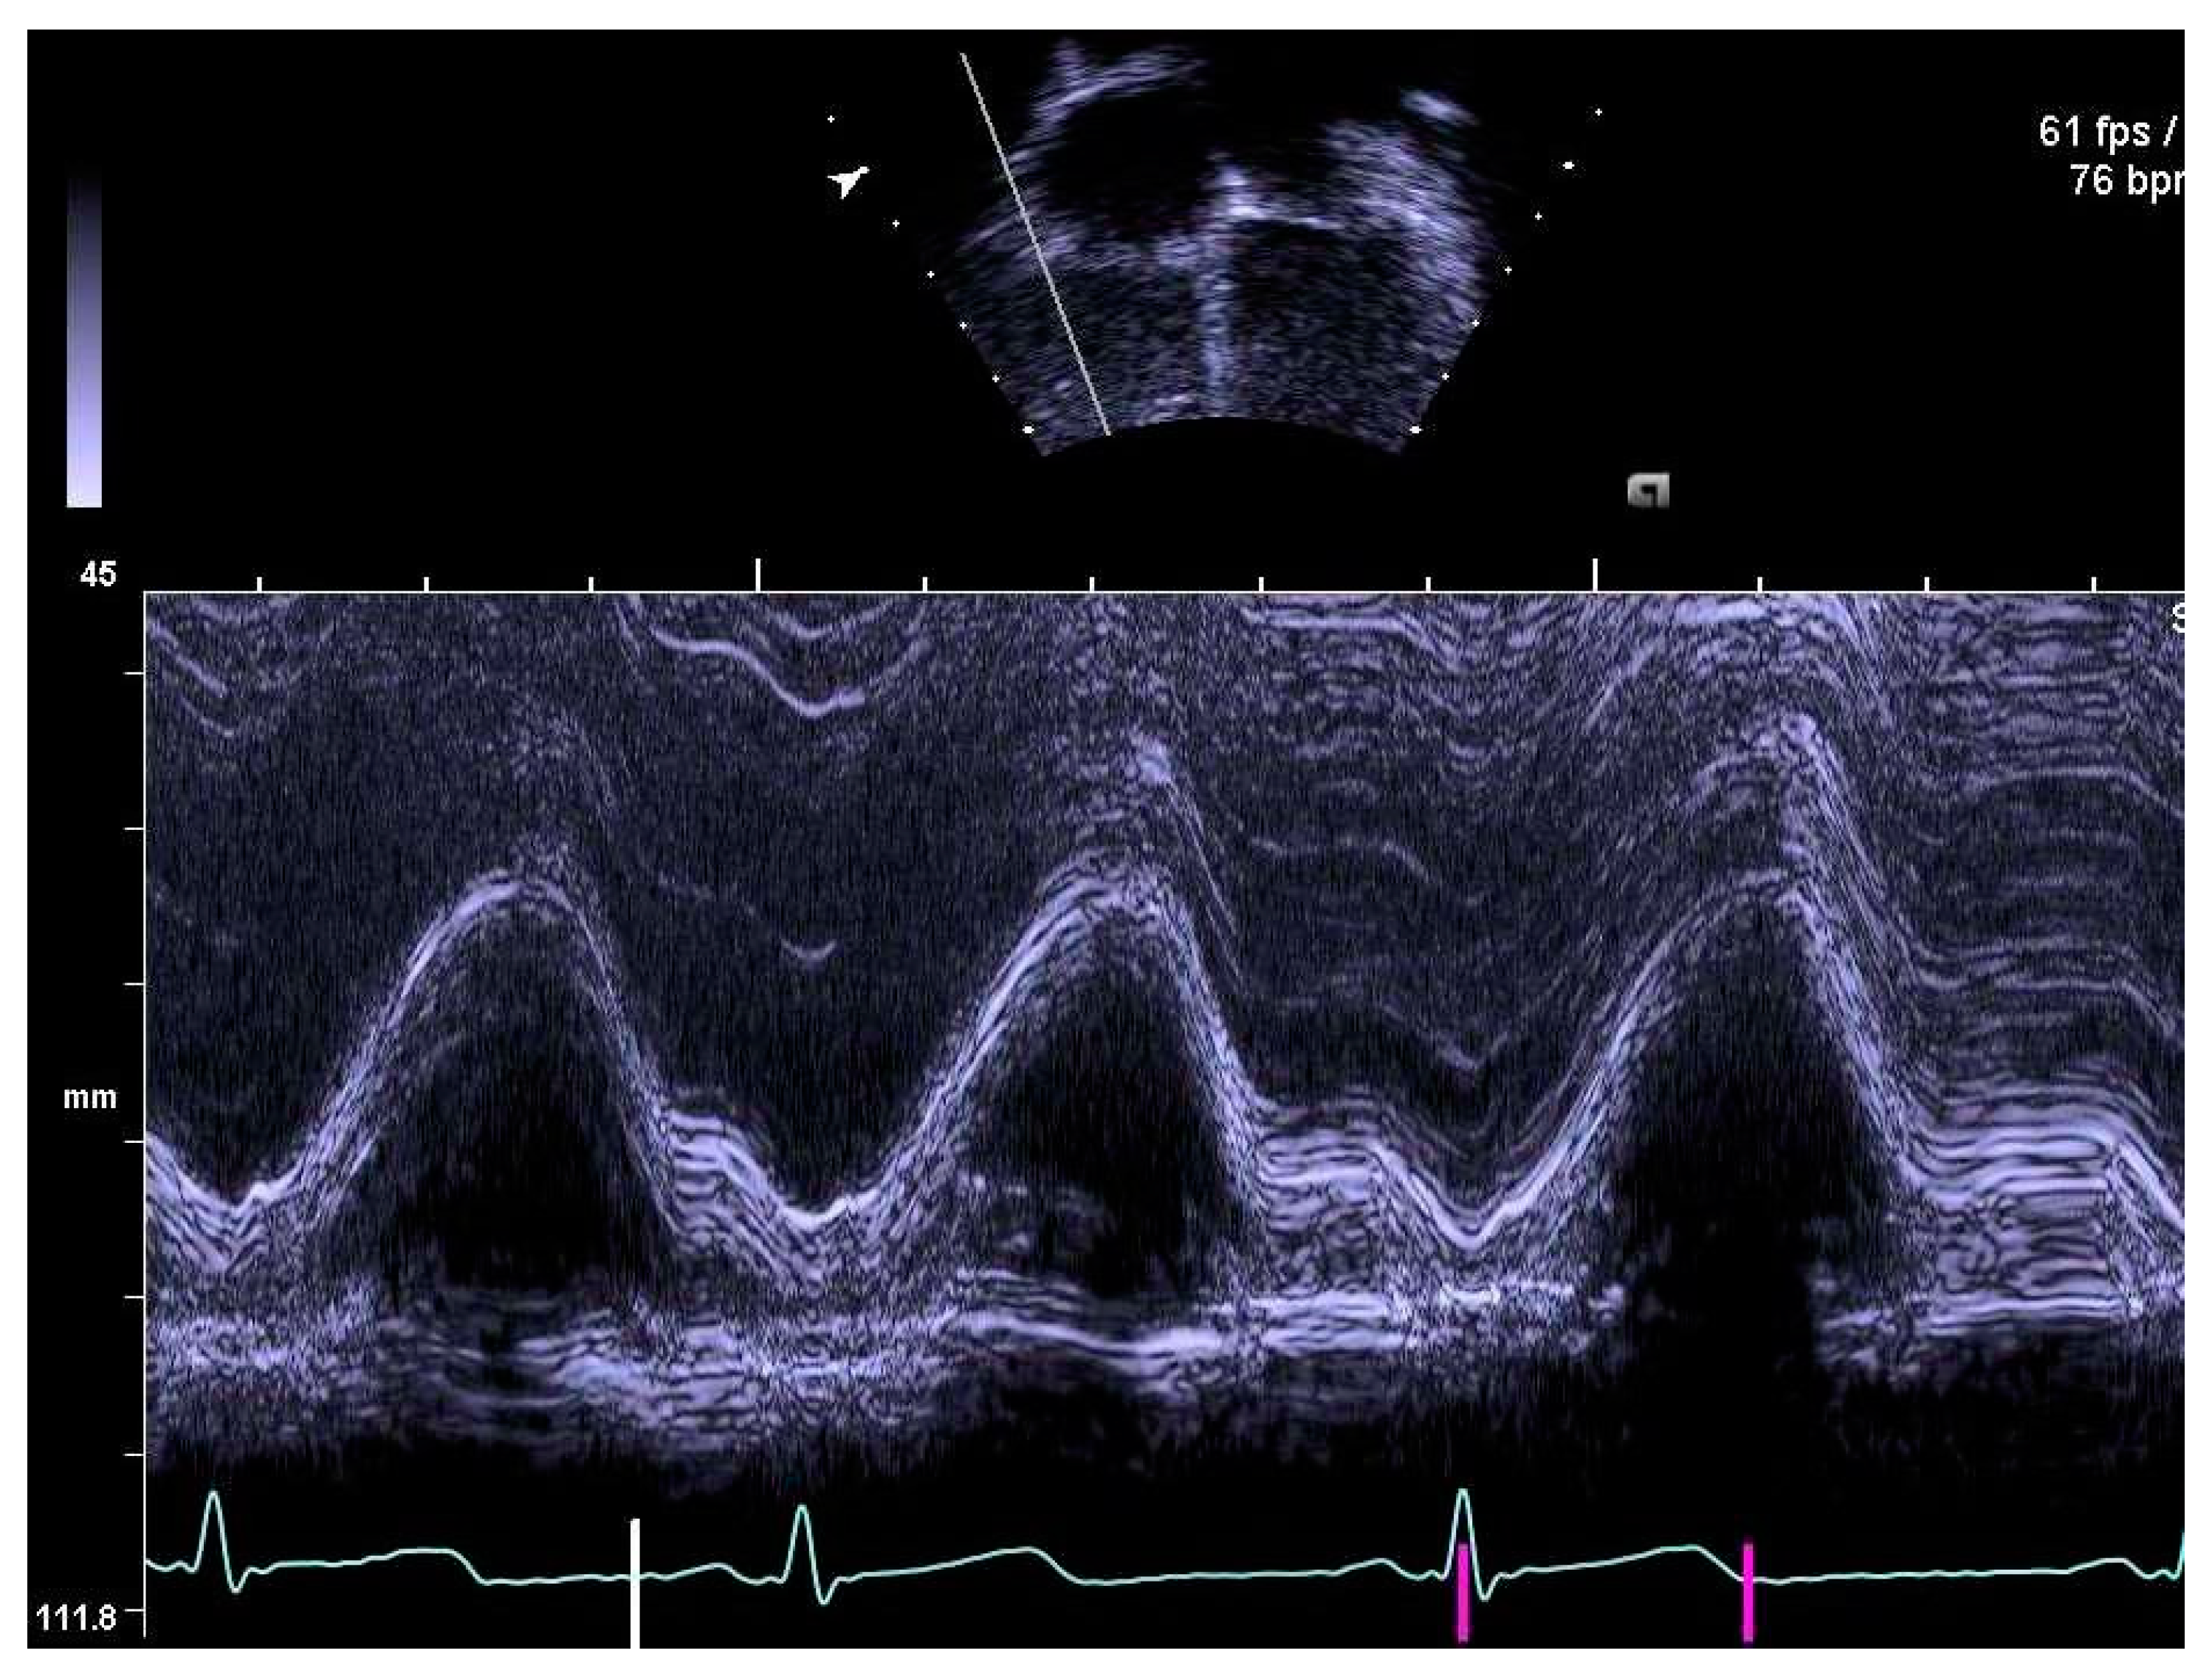

Figure 3.

Tricuspid annular plane systolic excursion, TAPSE, measured by M-mode.

The same experienced cardiac sonographer at each centre investigated all participants and followed a predefined standardized protocol. Image analyses of the right heart and the pulmonary arteries, as well as systolic and diastolic functions acquired with 2D echocardiography and blood- and tissue Doppler, were performed off-line by two operators: one (LAM) for recordings from Stockholm and Umeå, and another (OB) for Lund. Both operators were blinded to group belonging, and vascular dimensions as well as systolic and diastolic functions were determined using similar techniques as in previously reports of the systemic arteries and left heart [9,10]. RV volumes were calculated with velocity time integral for right ventricular outflow tract (RVOTvti) estimated by pulsed wave Doppler (PW) and pulmonary valve annulus diameter (PVann), Figure 1. RV relative wall thickness (RWT) was calculated as (anterior wall + interventricular septum)/ RV width. Sphericity index (SI) was calculated as diameters for length/width for the atrium and ventricle, respectively. Pulmonary vascular resistance (PVR) was estimated by Doppler, calculating the ratio using the simplified formula described by Abbas et al. 2003, for tricuspid valve regurgitation (TR), Figure 2, divided by RVOTvti [20]. Systolic function was evaluated by tricuspid annular plane systolic excursion (TAPSE), Figure 3 and diastolic function was assessed by early (E) and late (A) velocities of the tricuspid valve with pulsed wave and, with tissue Doppler (s’, e’, a’). To estimate RV filling pressure, the E/e’ ratio was calculated. Systolic ejection time (et), isovolumic relaxation time (ivrt) and isovolumic contraction time (ivct) were assessed with tissue Doppler to calculate right ventricular myocardial performance index (RVmpi’), using the formula (ivrt + ivct)/et, Figure 4.

Systolic function expressed as TAPSE was lower in EXPT compared with CTRL after adjustment. RV myocardial systolic velocity (s’) of the free wall and interventricular septum showed no differences between EXPT and CTRL. Adjusted RVmpi’ of the free wall assessed with tissue Doppler was slightly lower in EXPT than in CTRL.